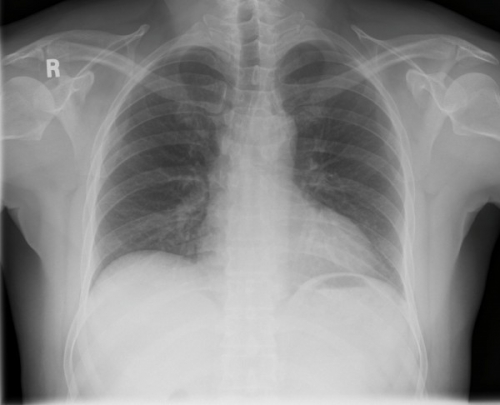

Tool to train medical student's eyes as to what a normal chest x-ray looks like, with over 500 consecutive normal images.